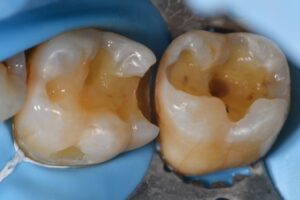

Determination of when to remove a peripheral rim enamel fracture hinges on whether the crack penetrates the DEJ, at which stage the risk:benefit ratio points to its removal. Caries is only detectable when it has reached 1/3rd the buccolingual thickness of the tooth, and it is not prudent to assume that it will express its breath first before deciding to penetrate deeper. Such superhighways for bacterial ingress should be removed.